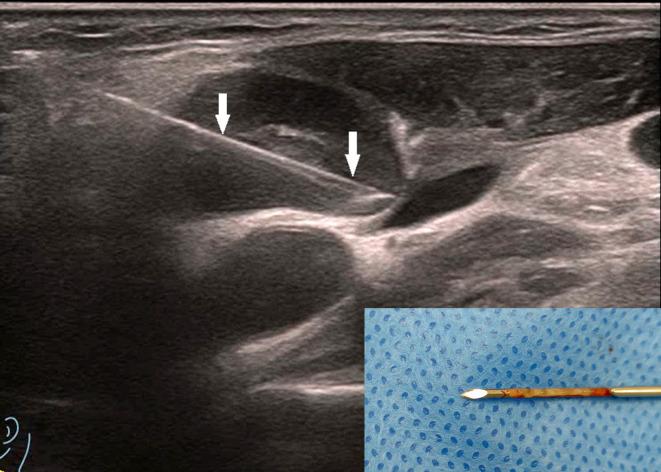

To investigate the value of contrast-enhanced ultrasound (CEUS) assisted core needle biopsy (CNB) in the diagnosis of cervical lymph node tuberculosis (LN TB) and improve the positive rate of cervical LN TB.

We retrospectively analyzed 730 samples obtained from July 2010 to January 2025 from patients treated with effective antituberculosis therapy and with microbiologically confirmed and surgical pathologically proven cervical lymph node enlargement who had undergone CEUS- CNB at our hospital. All patients were divided into two groups according to the historical control method. The CEUS group (2017-2025) underwent CEUS- CNB (485 cases), whereas the US group (2010-2018) underwent US-guided CNB (245 cases). The positive rates of pathological diagnosis and Xpert Mycobacterium tuberculosis complex (MTBC) and resistance to rifampin (RIF) (MTB/RIF) assay diagnoses were compared between the groups.

The specimens' integrity was significantly higher after CNB in the CEUS group than in the US group (CEUS group: 72.30%; US group: 45.49%), and visual satisfaction of sampling in the CEUS group was higher (χ2: 47.651, P < 0.001). Histopathological examination sensitivity, specificity, positive predictive value, and negative predictive value were higher in the CEUS group than in the US group. The sensitivity of the Xpert MTB/RIF assay was significantly higher in the CEUS group than in the US group.

The study results support the clinical use of CEUS for improving the diagnostic performance and positive rate for cervical LN TB.